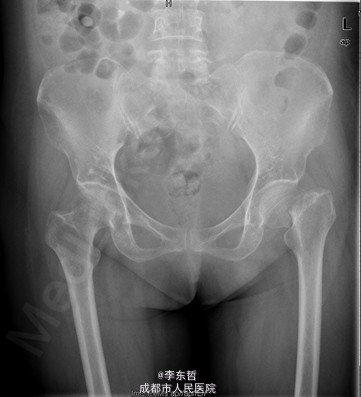

积极完善术前检查及准备后行左股骨颈骨折闭合复位DHS内固定术

随访无特殊